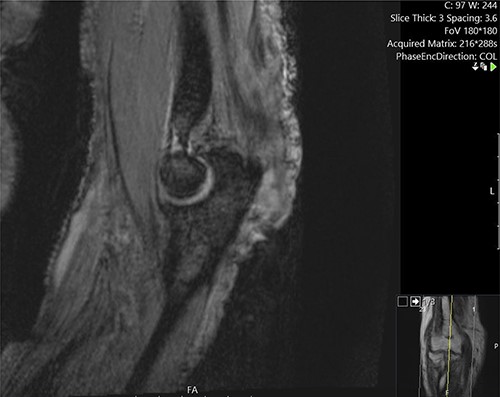

He was investigated with incisional biopsy of the lesion; four samples confirmed poorly differentiated cSCC. Further MRI imaging showed deep invasions of the cubital joint including, olecranon and ulna, and associated infiltration of the ulnar nerve and distal triceps (Figs 3 and 4). Positron emission tomography scan showed no distant metastases.

Cross-sectional MRI images demonstrating the position of the lesion and its infiltration into the joint space and deep tissues including the ulnar nerve.